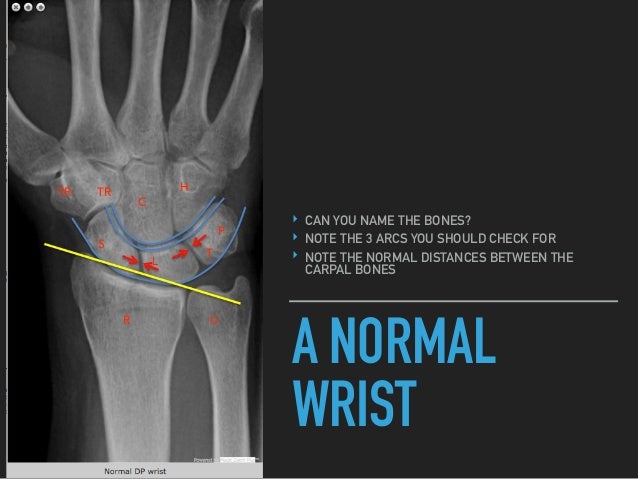

The angle of tilt is usually about 10 but ranges from 2 to 20. C capitate sits in the l lunate sits in the r radius apple c sits in the cup l sits in the saucer r c l r 23. Pretty pink rose tea cups saucer sets vintage made in china 4 sets s8902.

The radius r the saucer holds the lunate l the cup and the cup of the lunate contains the capitate c the apple.

Make offer vintage fire king green jadeite jane ray ribbed cup saucer coffee tea lot of 2. Franciscan ware apple pattern tea coffee cups and saucer. The articular surface of the radius has a slight but definite palmar ie anterior tilt.

A normal lateral very important for assessing dislocations can you name what you see. Royal stuart spencer stevenson white swirl w gold trim mcm cup saucer set. Shop for and buy cup and saucer online at macys.